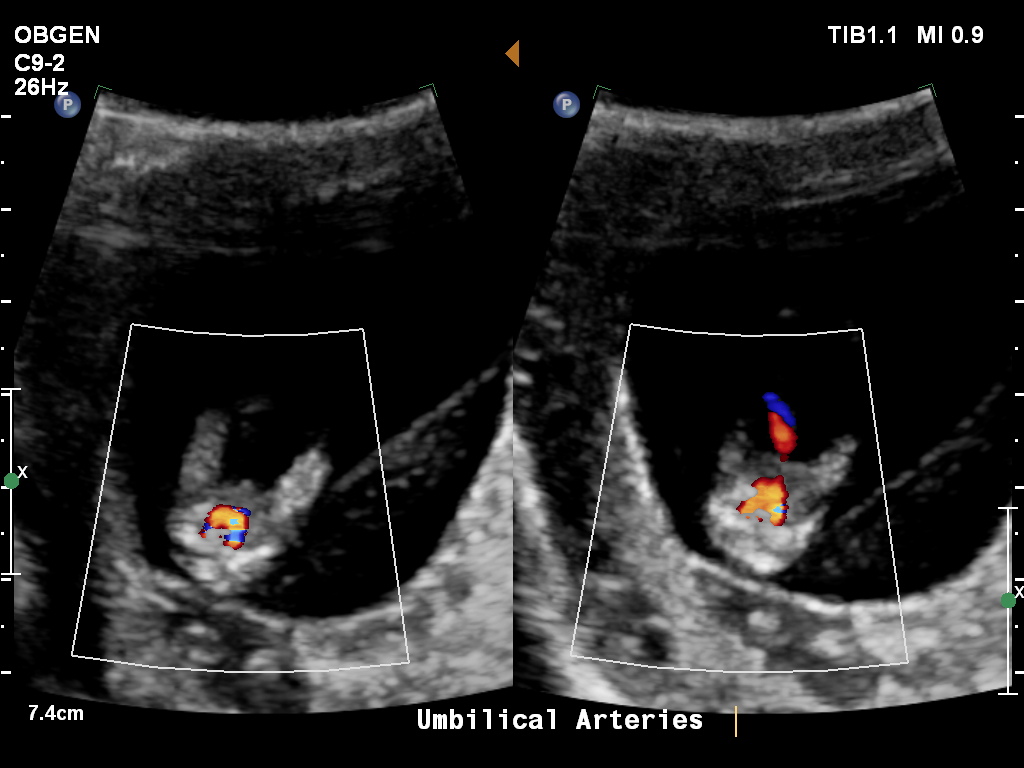

Here is the 'potty shot' Attachment 24670

Difficult to say, if the baby is actually 11+5, it could still be a boy and nub is on the rise, but if the baby is 12+4 then maybe girl, although the potty shot has a little thing sticking out.

So I'll go 50/50 on this one.

with bubs measuring behind, its hard to say. Potty shot at this stage they will all look alike so that ones out. Its girly for now but still very early to tell.